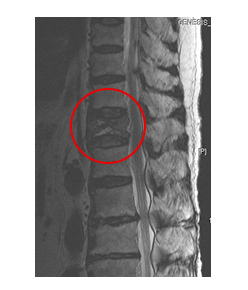

의사는 등과 허리검사와 진단을 위해 환자의 병력과 기저질환을 탐색하고, 이학적 검사와 신경학적 검진을 시행합니다. 단순 X-ray 촬영을 통해 간단하게 골절여부가 확인되지만 골절의 정도가 심하지 않거나, 다친 경험이 정확하지 않은 경우에는 정밀검사가 필요하기도 합니다.

또한, 신경손상등의 다른 심한 손상이 동반된 척추골절 분류에 포함되는지 확인하기 위해 허리검사 CT나 MRI 등의 정밀검사를 시행하기도 합니다. 급성 압박골절의 경우에는 허리 골절 수술을 시행하지 않더라도 MRI의 급여 적용이 가능합니다.

그러나 2주 경과후에도 통증이 진행되거나 지속되고 골절된 척추 뼈가 계속 주저앉아 압박골절의 정도가 심해지면 (X-ray촬영으로 압박률 확인) (풍선) 척추성형술을 시행하게 됩니다.